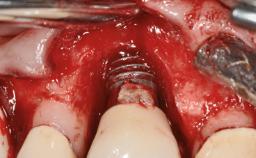

Oral Lichen Planus Associated with the Peri-implant Mucosa

This case describes the ongoing management of a 64-year-old healthy, non-smoking female patient with erosive oral lichen planus (OLP) affecting the gingivae and the buccal and lingual mucosa. The peri-implant mucosa was also affected subsequent to implant placement. The patient had osseointegrated implants (four in the maxilla, four in the mandible) placed following extraction of hopeless teeth and a healing period. The patient had a history of OLP prior to implant placement and had been referred to an oral-medicine specialist for definitive diagnosis and treatment. She exhibited generalized oral mucosal involvement. Following a clinical assessment, biopsy, and blood tests, she was treated with topical corticosteroids. Systemic prednisolone was reserved for severe flare-ups. Amphotericin lozenges were used in combination with corticosteroid treatment to prevent the development of oral candidiasis.